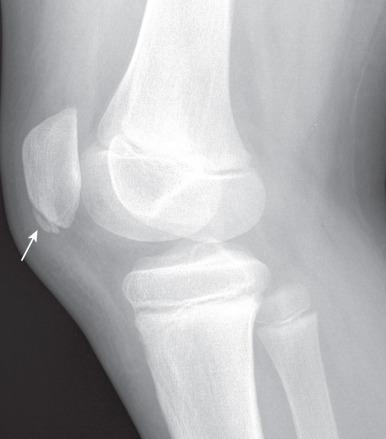

Ларсена йохансона

Ларсена йохансона 146 фото